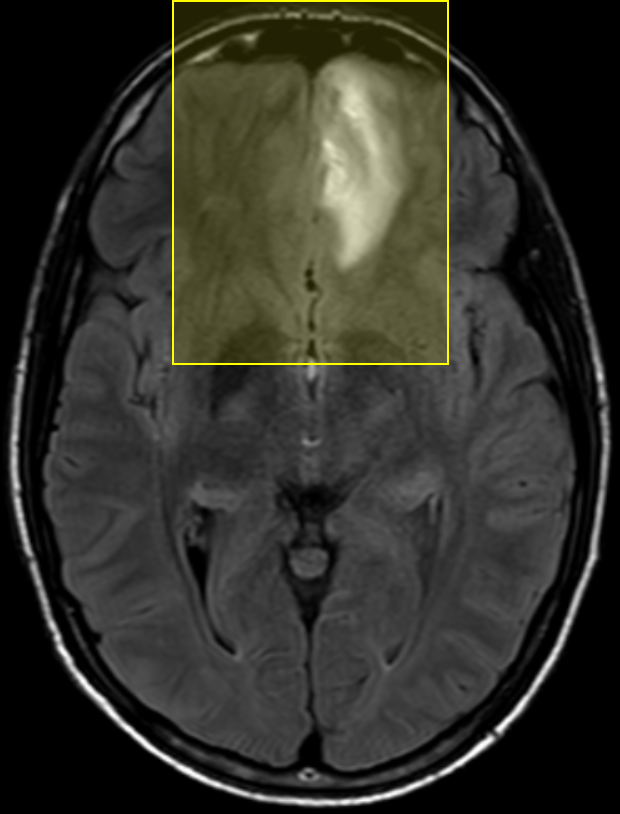

We performed pairwise comparison between two scans of a 32-year-old basketball player, diagnosed with mild occipital traumatic brain injury and frontal hemorrhage due to contrecoup impact, acquired one week and 6 months post-injury. The hemorrhagic lesion at the frontal right hemisphere of the player is no longer visible in the FLAIR image acquired 6 months after injury (Fig. 2a). Local differences between corresponding, longitudinal FA- and MD-FFDD profiles of the FMT (chosen due to its proximity to the lesion area) are shown in Fig. 2d. Figs. 2b-c present color-coded FMT to visually demonstrate these differences. Results show significant longitudinal variability at the right hemisphere part of the tract, corresponding to the lesion area, and relatively minor differences along the rest of the tract. These results should be considered as a proof of concept, validating the FFDD analysis results for the detection and localization of mTBI-related variabilities between fiber bundles.

| ONE WEEK | ![]() |

![]() |

FA-FFDD |

| 6 MONTHS | ![]() |

MD-FFDD |

| (a) FLAIR | (b) FA-FFDD | (c) MD-FFDD | (d) Local Differences |